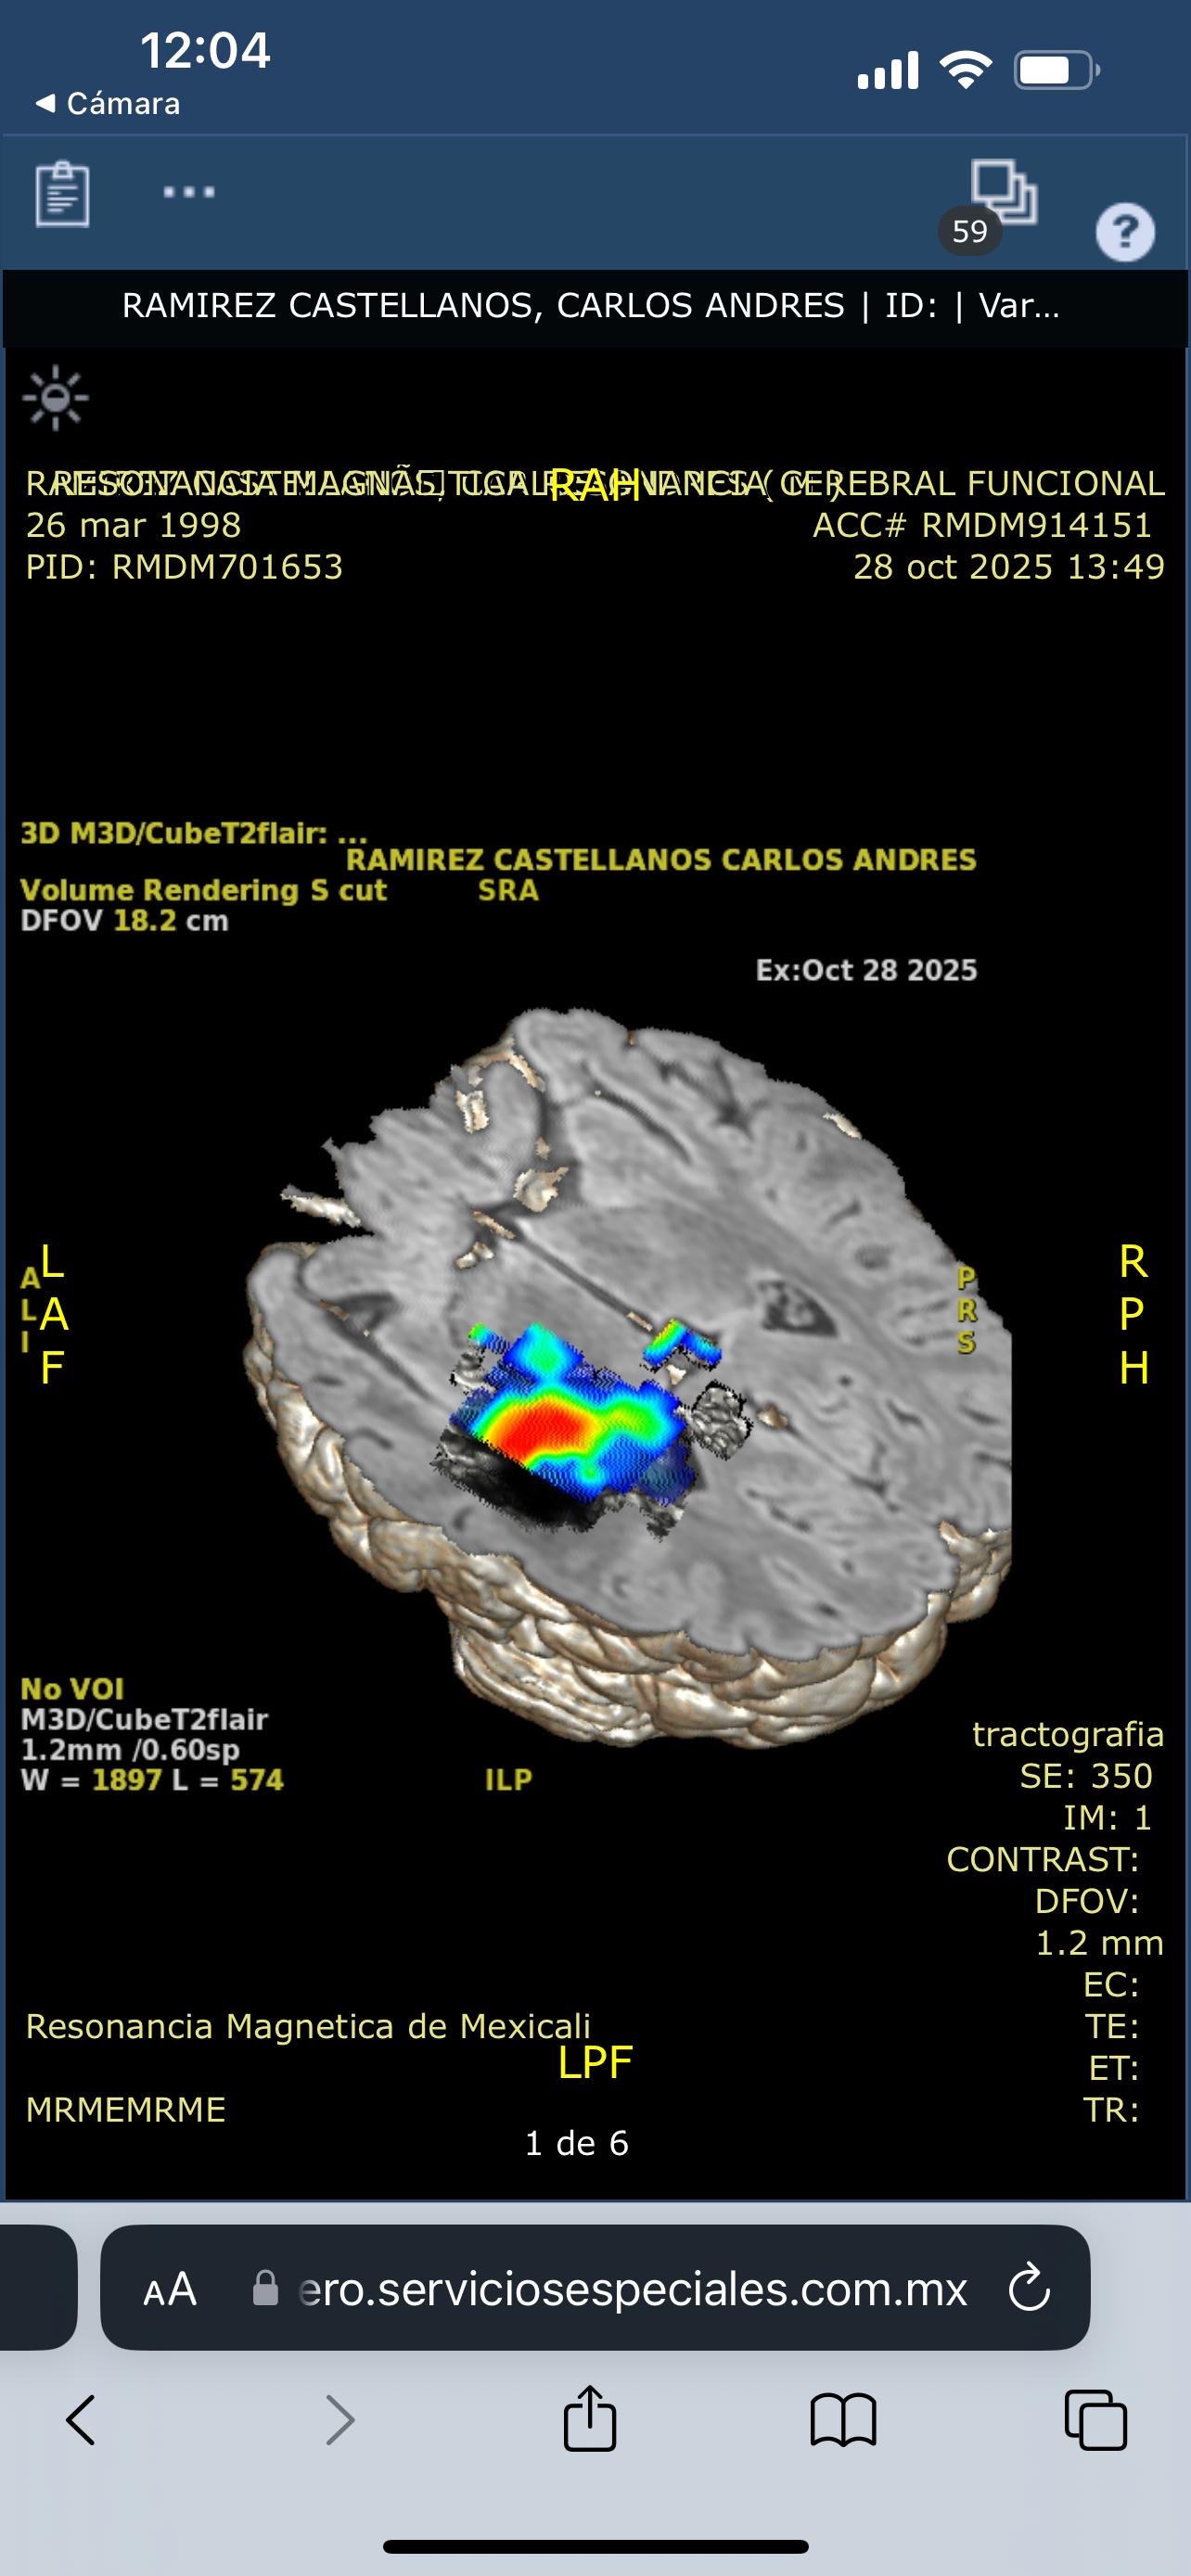

Hoy, lamentablemente, Carlos enfrenta una de las pruebas más difíciles de su vida. Fue diagnosticado con una hemorragia cerebral, una condición grave que avanza rápidamente y requiere una cirugía urgente para salvar su vida.

Today, Carlos is facing one of the toughest battles of his life. He was recently diagnosed with a brain hemorrhage, a serious and rapidly progressing condition that requires urgent surgery to save his life.